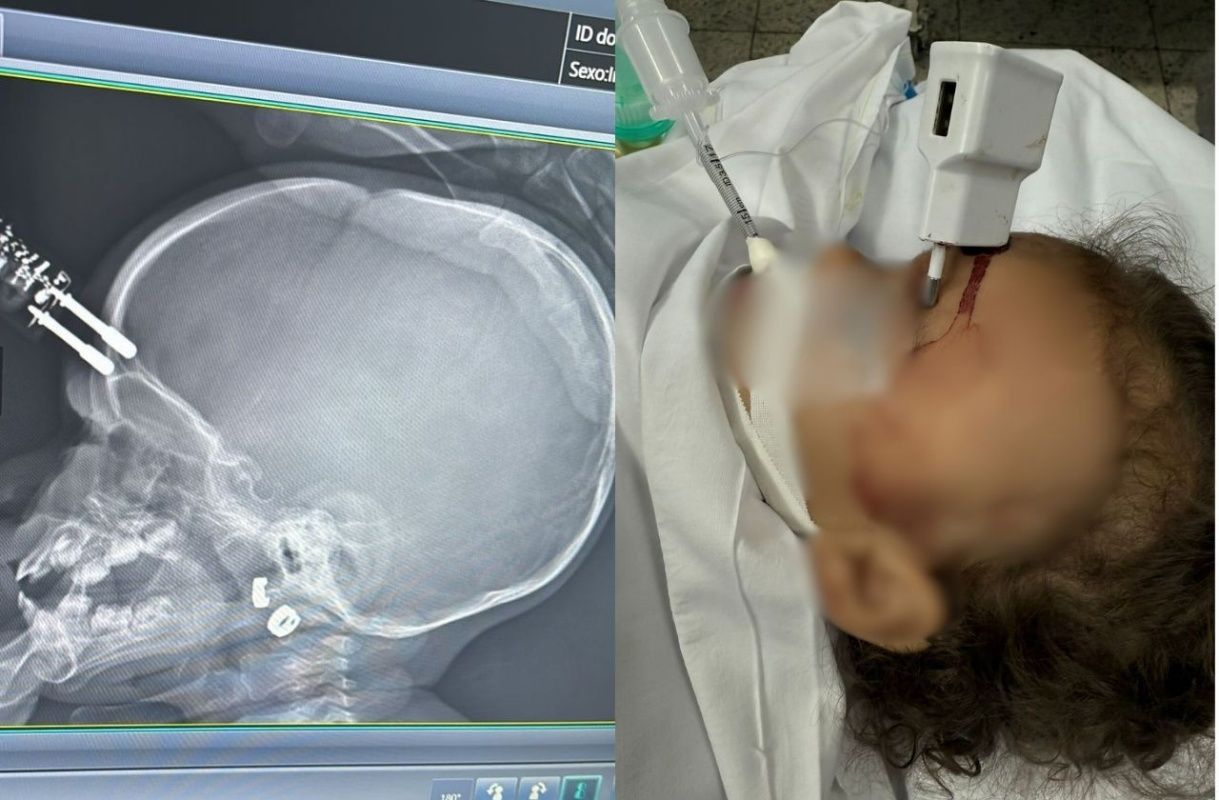

Bebê fica com carregador de celular preso na testa após cair de cama

A bebê ficou com um carregador de celular preso na testa após cair de uma cama e precisou passar por uma cirurgia de emergência

Uma bebê de 1 ano e quatro meses ficou com um carregador de celular preso na testa após cair de uma cama e se acidentar. A criança precisou ser submetida a uma cirurgia de emergência para retirada do equipamento.

O caso aconteceu na cidade de Divinópolis, na região oeste de Minas Gerais. O carregador estava em um colchão, colocado embaixo da cama onde a criança estava. Como ficou cravado na cabeça da bebê, o objeto precisou ser retirado via procedimento cirúrgico.

De acordo com a mãe, ela foi ao banheiro e deixou a filha sozinha na cama por alguns instantes. Logo depois, ouviu o choro da menina e a encontrou no chão, com os pinos do carregador cravados na testa. Segundo o SBT News, o acidente ocorreu na noite de segunda-feira (12).

Ela acionou o Samu, que realizou o atendimento e encaminhou as duas para a UPA. Segundo o neurologista Bruno Castro, que atendeu o caso, o carregador chegou a perfurar o crânio da menina, provocando uma fratura.

Ela foi inicialmente atendida na Unidade de Pronto Atendimento (UPA) de Divinópolis e, em seguida, transferida para o Hospital São João de Deus, onde passou por cirurgia imediata para retirada do objeto, correção da lesão e contenção de um pequeno sangramento.

Após o procedimento, a criança foi levada ao Centro de Terapia Intensiva (CTI), onde permaneceu por 36 horas. Ela passou por tomografia de controle e apresentou boa evolução clínica.